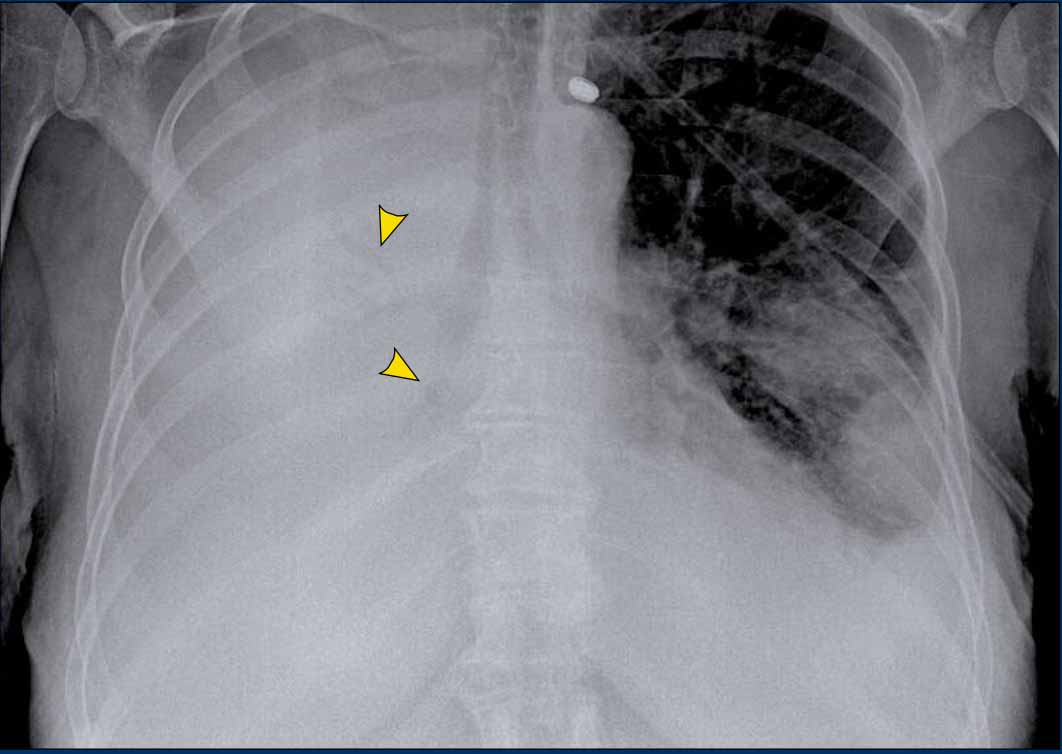

Hidden Areas (3): Pneumonia Below the Diaphragm

In this case, a pneumonia was primarily located below the right diaphragmatic dome (yellow arrow), within the posterior basal segment of the right lower lobe.

• On the lateral view, there is an increase in opacity over the lower thoracic vertebrae, indicating lower lobe consolidation (arrow).

• Again, image magnification may be necessary for adequate assessment.